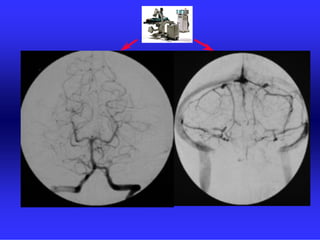

METODE PRIKAZA KRVNIH ŽILA

•UZ-DOPPLER

•DSA

•CTA

•MRA